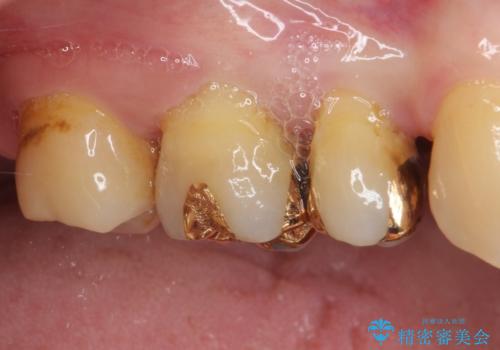

- 奥歯の裏側がしみるとのことで来院された患者様です。

矯正治療による歯肉退縮がおき、歯根にまで虫歯が波及していました。

虫歯が大きかったため、フルジルコニアクラウンにて補綴することとしました。

一部歯肉の中にまで虫歯が波及しており、汚れが溜まりやすくなっていましたが、クラウン装着後は汚れが溜まることはなくなりました。